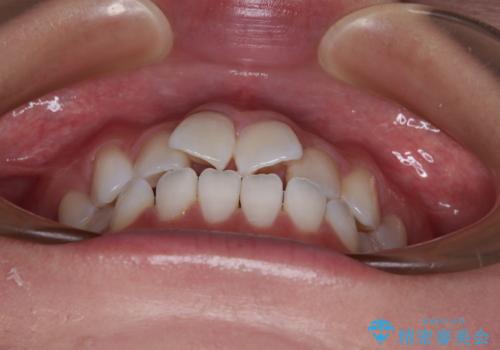

- 上下前歯のデコボコを気にして来院された患者様です。

ワイヤー矯正でもマウスピース矯正でも可能でしたが、短期間で、自身の手を煩わせることなく治療を行いたいとのことで、ワイヤー装置にて矯正治療を行うこととしました。